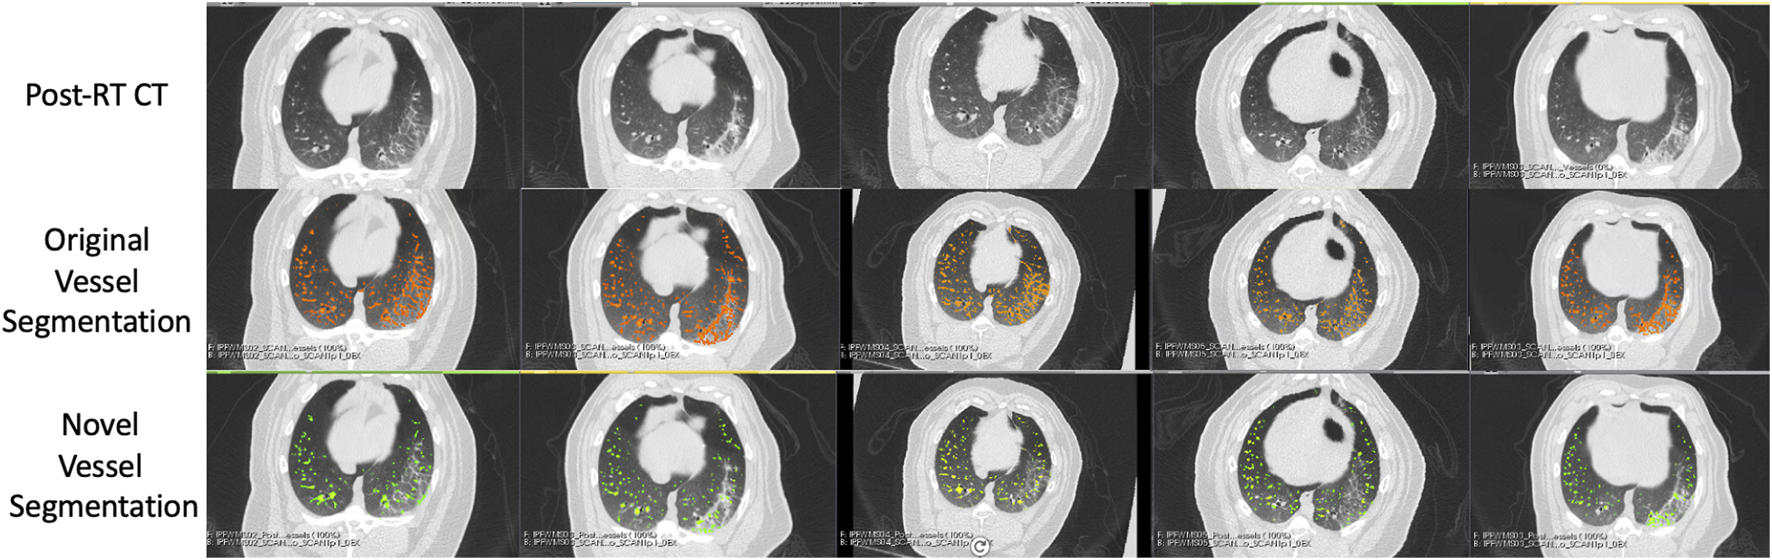

An example of the vessel segmentation algorithm is shown in Figure 5. The post-RT original vessel segmentation classifies regions of radiographic change as vessel. When removing the ground glass reticular and bronchovascular voxels, in both the pre and post-RT examples it is observed that the larger vessels are no longer segmented. In the post-RT case it can also be seen that the radiographic change region is no longer classified as vessel. When large vasculature is added back in both pre and post-RT resultant vessel maps appear to be consistent with the vessels observed on the original CTs. Figures 6, 7 show the improvements made by the novel vessel segmentation in an axial slice of all of the subjects used in this work. In all subjects, it is clear that radiographic change is falsely classified as vessel in the original vessel segmentation method. This is further highlighted in Figure 8 where a side by side 3D rendering shows the effect of this false classification. The conventional method, in the regions denoted as having radiographic change, are so over-segmented that you cannot distinguish the true vasculature in this region and it just appears as a large condensed structure. However, when using the novel segmentation workflow presented in this work, we see that it appears specificity is improved in those regions of radiographic change while preserving the sensitivity of the segmentation in the rest of the lung. The improved workflow 3D rendering shows a connected vascular tree in these regions. In the group B swine, the result is more subtle but this is due to the fact that the radiographic change in these swine was not as drastic as the group A swine in a single axial slice. This is due to the differences in dose distribution delivered as well as differences in the size of vasculature irradiated.

FIGURE 6

Segmentation results in the five Group (A) swine. Each column represents a subject where the top row shows the post-RT CT image in an axial slice showing the post-RT radiographic change. The middle row shows the original vessel segmentation overlayed on the CT in red which in all subjects classified damaged regions of the lung as vessel. The bottom row shows the result of the novel vessel segmentation workflow overlayed on the CT in green. In all subjects, the apparent quality of the vessel segmentation improves in the regions of radiographic change as indicated by the reduction in large connected regions being identified. The resulting segmentation appears to align with vessels that can be observed in the CT in both irradiated and non-irradiated regions.

FIGURE 7

Segmentation results in the five Group (B) swine. Each column represents a subject where the top row shows the post-RT CT image in an axial slice showing the post-RT radiographic change. The middle row shows the original vessel segmentation overlayed on the CT in red which in all subjects classified damaged regions of the lung as vessel. The bottom row shows the result of the novel vessel segmentation workflow overlayed on the CT in green. In all subjects, the apparent quality of the vessel segmentation improves in the regions of radiographic change as indicated by the reduction in large connected regions being identified. The resulting segmentation appears to align with vessels that can be observed in the CT in both irradiated and non-irradiated regions.